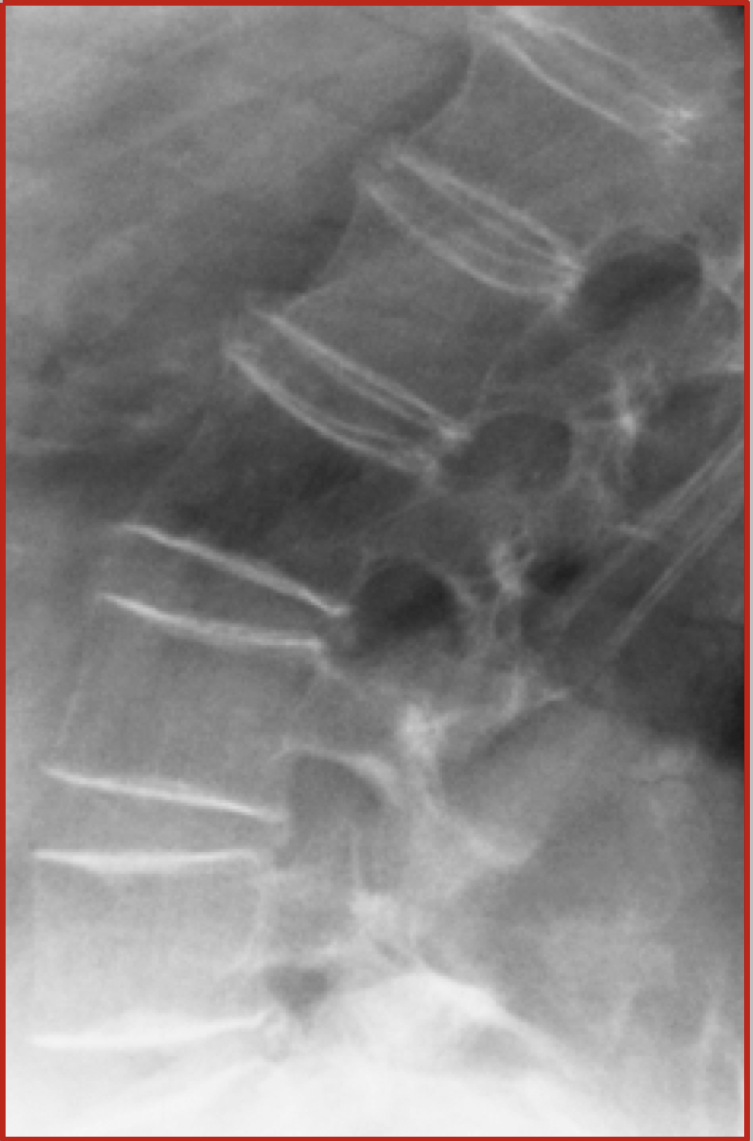

_________ refers to bones that are brittle and fracture.

Osteoporosis

________ refers to bones that are soft and bend.

Osteomalacia